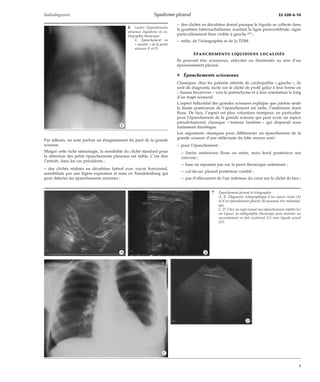

20 Mésothéliome malin : sujet retraité ayant été exposé à l’amiante.

A. Radiographie thoracique : hémirétraction thoracique droite.

B, C. Tomodensitométrie : épaississement nodulaire circonférentiel (B) et scissuraire (C).

D. Imagerie par résonance magnétique : extension transdiaphragmatique (flèche).

épanchement peut être isolé, associé à des lésions nodulaires,

tissulaires ou pleurales, ou à des épaississements pleuraux diffus.

21 Carcinome thymique avec métastase pleurale (circonférentielle) : aspect pouvant faire discuter un mésothéliome

ou un adénocarcinome pleural.

A. Radiographie thoracique : hémithorax rétractile et « engainement » pleural.

B, C. Tomodensitométrique : masse thymique et nodulations pleurales et scissuraires.

*A

*B *C